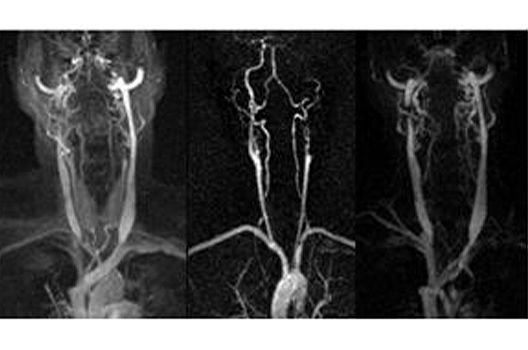

Der ständige Einstrom des Blutes in ein ausgewähltes Volumen oder die zeitweise Beschränkung der Ausbreitung von intravenös gegebenen Kontrastmittel auf die Gefäße kann bei einer geeigneten Wahl der Messsequenzen dazu benutzt werden, Darstellungen von Gefäßen in dem Volumen zu erzeugen. Dabei macht es die Fülle von arteriellen und venösen Gefäßen häufig erforderlich, eine Auswahl bei dieser Darstellung zu treffen, weil sich sonst einzelne kleine Gefäße häufig nicht mehr identifizieren lassen. Die Realisierung einer solchen Auswahl ist abhängig von der Wahl der verwendeten Messtechnik. Bei der Time-of-Flight-Angiographie. die auf dem Einstrom von ungesättigtem Blut in die angeregte Schicht beruht, kann die unterschiedliche Richtung der Flussgeschwindigkeit für eine selektive Sättigung benutzt werden. Wenn der Kontrast in den Gefäßen durch die Gabe von Kontrastmitel produziert wird, kann der zeitliche Verlauf der Kontrastmittelverteilung in den Gefäßen für eine Separierung herangezogen werden.

In einem aktuellen Forschungprojekt soll die Qualität von MR-Angiographien in spezifischen klinischen Fragestellungen durch eine Optimierung von Messparametern und Auswerteverfahren verbessert werden.